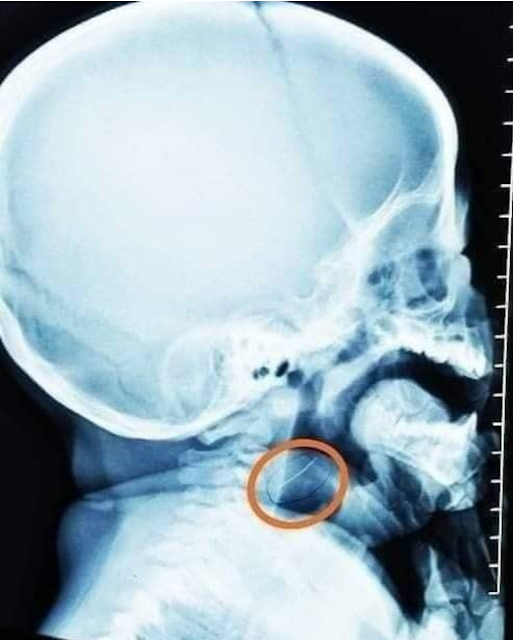

Ayon sa isang facebook page na 'Doctor Parenting' makikita ang larawan ng isang batang nakahiga, ang X-ray result nito at ang wire na nakuha sa kanyang katawan.

Ayon sa nasabing post ginamit ang sira sirang strainer upang durugin at mapino ang pagkain ng bata.

Ayon sa report ay matagumpay na natanggal ang maliit na wire sa lalamunan ng bata at sa ngayon ay nasa mabuti ng kalagayan.